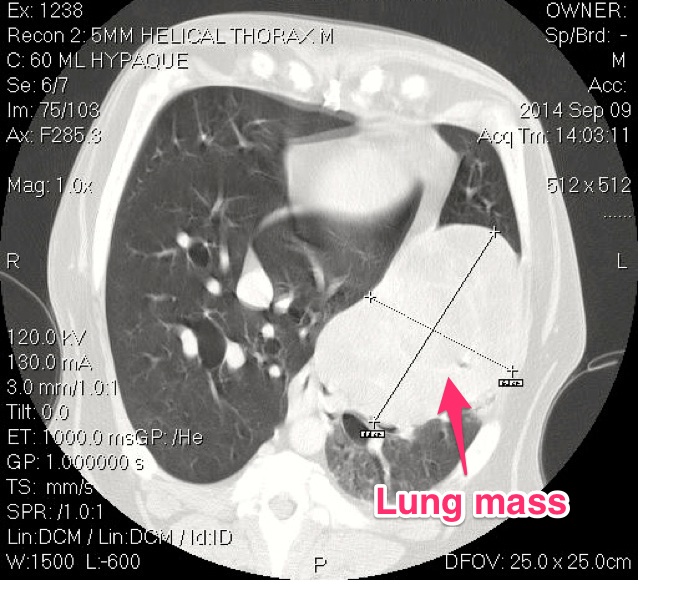

The typical way to diagnose a primary lung tumor is with radiographs (x-rays) of the chest. If a large solitary mass is seen, it is suspected to be a primary lung tumor. Another was to visualize a primary lung tumor would be to perform a CT (computed tomography) scan of the chest. A CT scan gives us excellent detail of the mass and allows a very in depth view of the rest of the lung tissue for evaluation. Some advocate for a fine needle aspirate of the mass (sticking an needle in the mass to get a representative sample of cells) prior to discussing surgery. Typically a solitary lung mass will be a pulmonary adenocarcinoma and a fine needle aspirate will only yield a diagnostic result only 60-70% of the time. Many believe (myself included) that surgery is the next step for a diagnosis. Prior to surgery a minimum staging database should be acquired. This includes (in addition to chest x-rays and/or chest CT scan) complete bloodworm with urinalysis and an abdominal ultrasound (or contrast CT scan). This is to evaluate body organ function and the presence of metastasis or other non-related issues, since most patients with a primary lung tumor fall into the geriatric age category, it is not uncommon to uncover other issues.